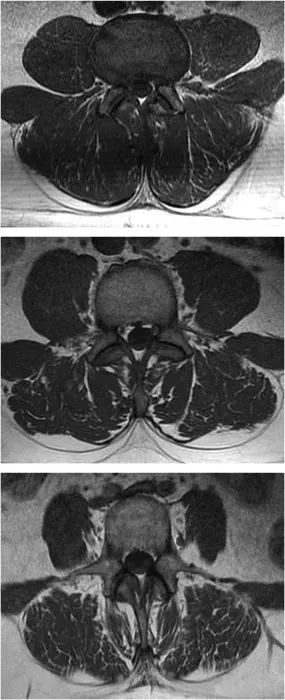

放射學文獻報告了在慢性腰背痛中,出現(xiàn)了腰椎多裂肌的脂肪浸潤,有證據(jù)表明在MRI上看到的非收縮組織實際上是脂肪。脂肪浸潤和組織重塑可能與萎縮無關(guān)。

圖 3展示了腰椎多裂肌中的脂肪浸潤。腰椎L3節(jié)段的腰部多裂肌輕度(<10%)、中度(10–50%)和嚴重(>50%)脂肪浸潤的T1加權(quán)MRI圖像示例.